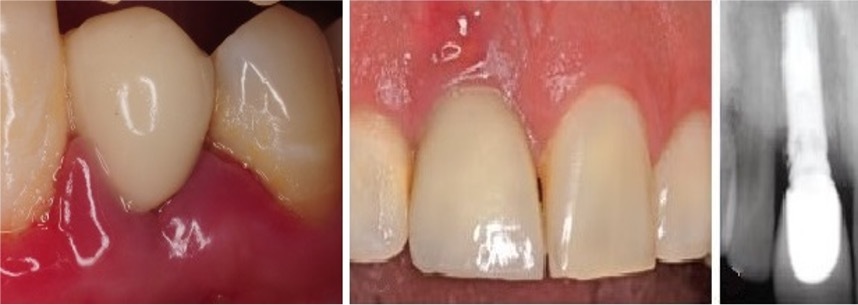

Q

What does this image depict?

A

Radiographic appearance of a cylindrical root form implant